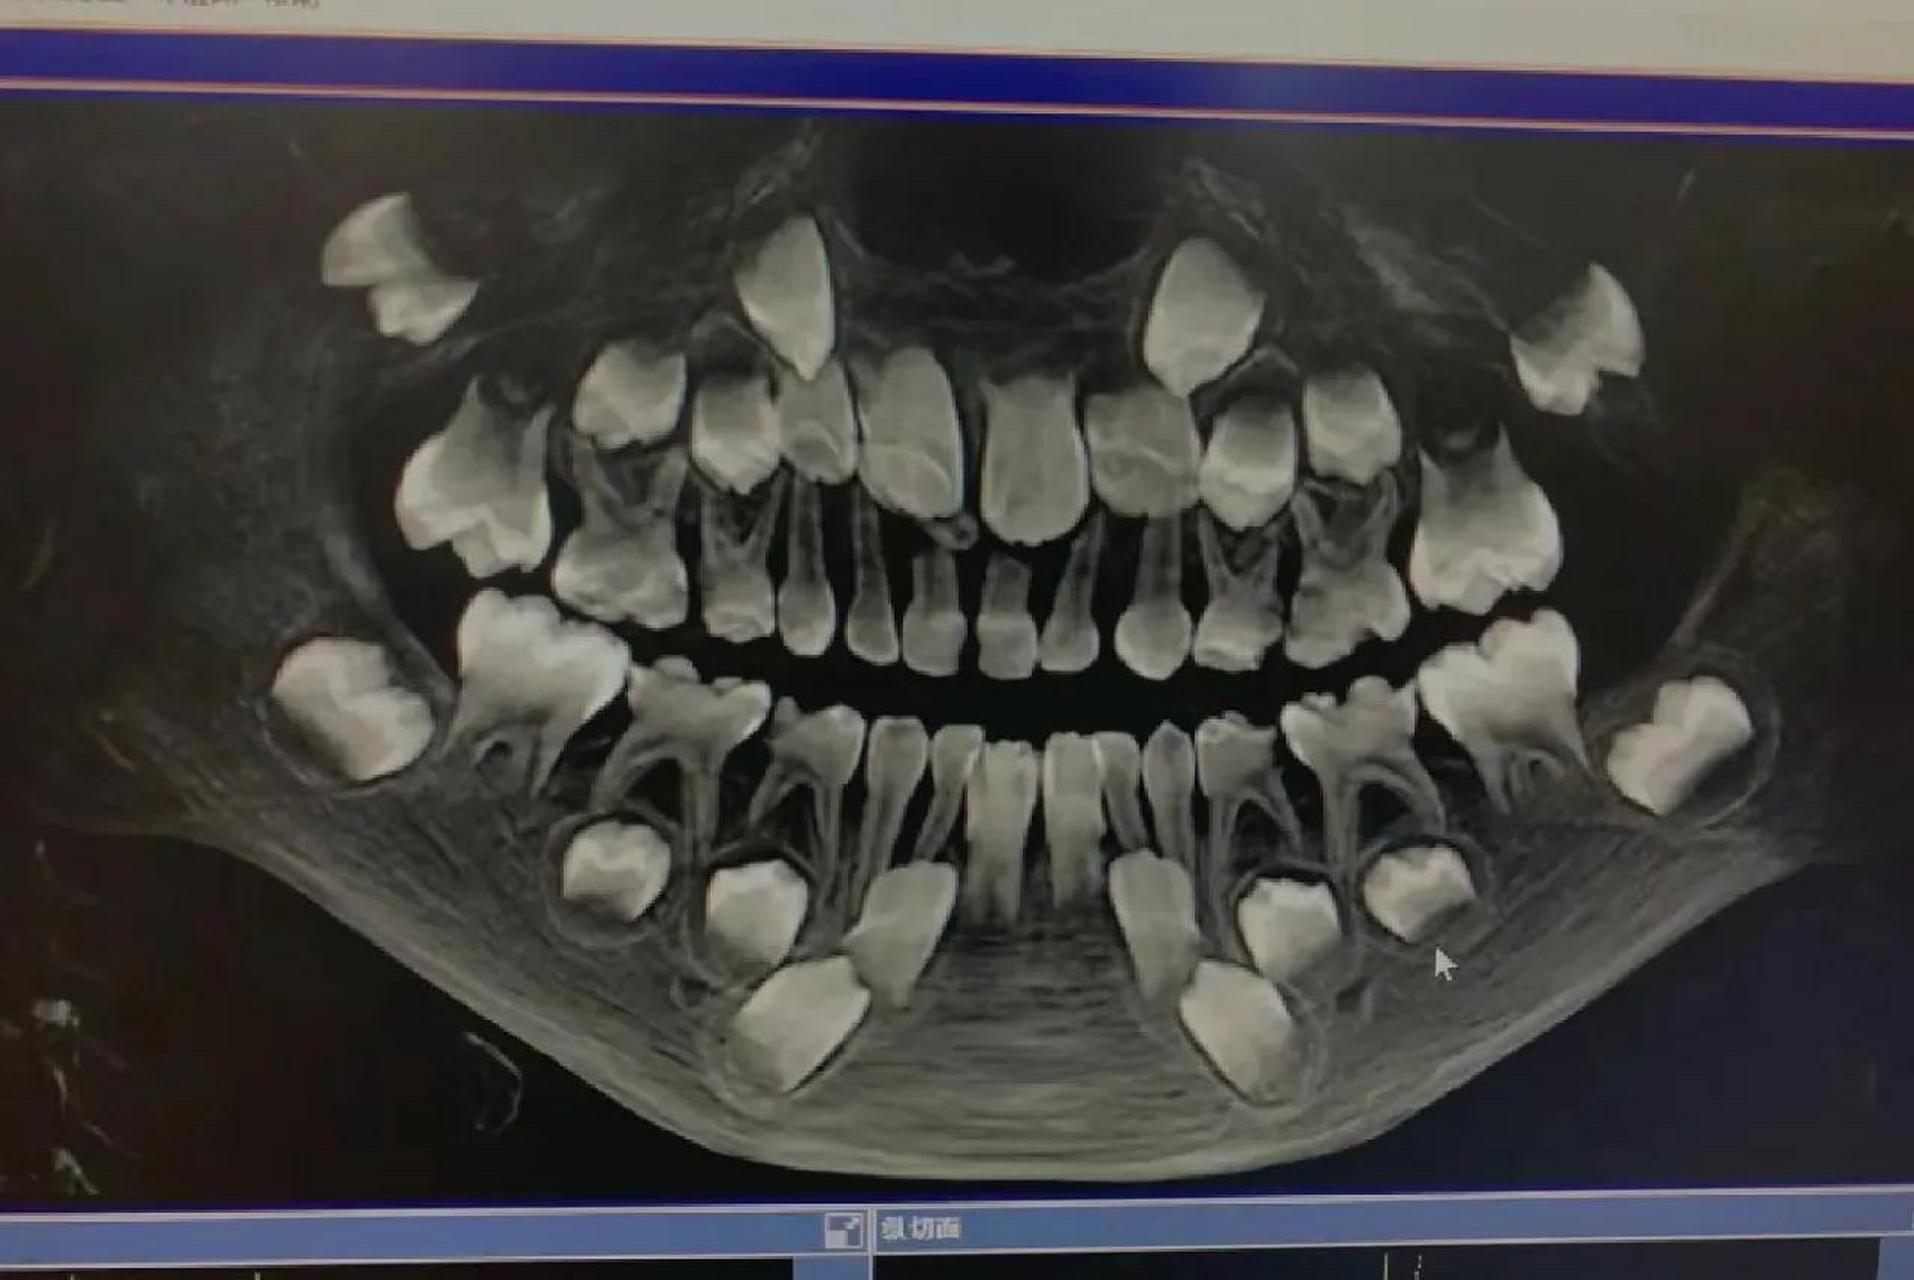

换牙期小朋友的牙片可以清楚看到有四排牙齿 (还有两颗是长在眼睛下方

图片尺寸1734x1280